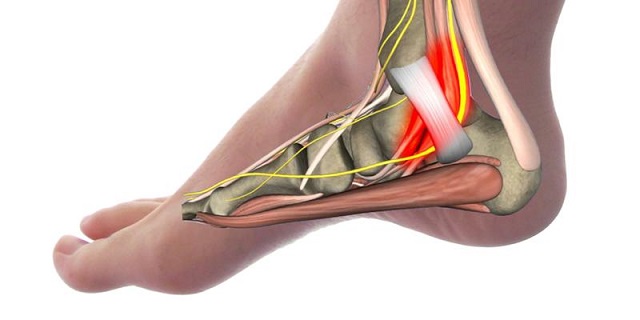

Скелет стопы состоит из двадцати шести костей, что удивительно для такой небольшой структуры. Пяточная кость — самая крупная из них. Она имеет губчатую структуру и удлинённое, сжатое по бокам тело. Спереди пяточная кость соединяется с кубовидной, сверху — с таранной, а сзади у неё есть выступ — пяточный бугор, к которому прикрепляется самое мощное сухожилие в организме — ахиллово. В нижней части пятки находится жировая прослойка толщиной 1-1,5 см, содержащая сеть сосудов и нервов. Эти структуры могут воспаляться, что часто приводит к болям в пятке и дискомфорту при ходьбе.

Задняя и боковые поверхности пяточной кости практически не защищены: кожа здесь тонкая, жировая клетчатка минимальна, а количество сосудов и нервных окончаний велико. Поэтому ушибы и подвывихи, которые происходят с каждым человеком, могут вызывать значительные страдания и долго не проходить. Полноценные вывихи, переломы, растяжения и разрывы связок также добавляют к этому списку.